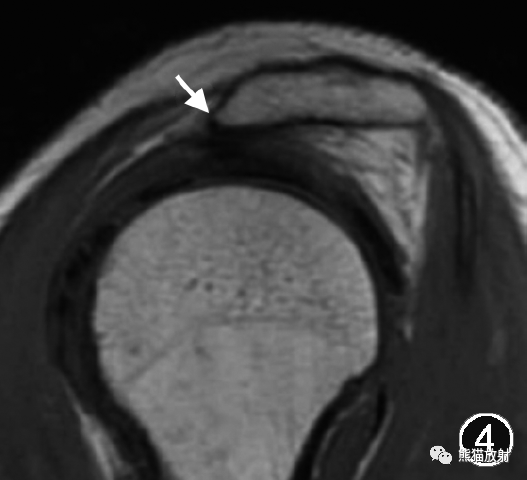

肩峰下骨刺常提示存在长期的慢性撞击(图5,6)。

图5,6 肩峰下骨刺伴肩峰下撞击综合征的MR图像。肩关节MR平扫斜冠状面T1WI(图5)和脂肪抑制T2WI(图6)示肩峰下缘增生骨赘(↑),肩峰下间隙狭窄,冈上肌腱增粗、信号增高(△),肩峰下-三角肌下滑囊积液